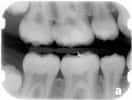

Bite-wing X-ray

highlight the crowns of the back teeth. Dentists take one or two bite-wing X-rays on each side of the mouth. Each X-ray shows the upper and lower molars (back teeth) and bicuspids (teeth in front of the molars). These X-rays are called "bite-wings" because you bite down on a wing-shaped device that holds the film in place while the X-ray is taken. These X-rays help dentists find decay between back teeth.